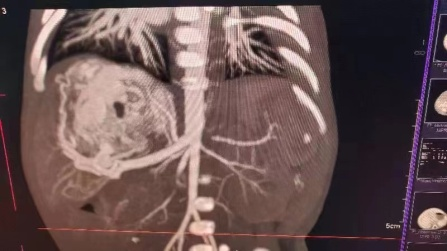

患儿妈妈怀孕期间产检发现肝脏占位,血运丰富,并随着时间的推移,肝脏占位逐渐变大,孕38+5周外院彩超提示肝脏肿块增长至7.3*4.3cm。宝宝出生后第一天即出现拒乳、呼吸困难、心率快等表现,考虑宝宝的情况为肝脏的血管瘤并有肝动-静脉瘘,引起心脏持续高动力状态,导致心功能不全,这是一种能够危急患儿生命的紧急情况,需要及早干预治疗,家属遂即慕名转至我院新生儿科。入住新生儿科后王惠萍教授紧急联系B超室乞艳华副教授完善心脏以及肝脏彩超评估患儿心功能以及瘤体大小,宝宝的肝脏占位正逐渐增大,心功能逐渐恶化,留给家属和医生的时间正在减少;小儿外科高亚教授心系患儿安危,多次查看、询问患儿情况,并根据每次复查指标,作出指示:决定使用微创介入的方式进行肝动脉栓塞术,封堵肿瘤血供。但新生儿血管纤细,动静脉瘘广泛,新生儿设备、管路、用药禁忌等诸多难题,成功的案例国内外鲜有报道,西北地区尚无类似病例报道。为了给患儿争取生存的机会,组织影像科介入组、小儿外科、麻醉手术科、医用超声科、新生儿科等院内多学科MDT团队进行了评估以及手术方案讨论, 反复论证手术的可行性,提出手术可能存在的风险以及应急策略并做好充分准备。

3月13日,在小儿外科高亚教授、郑百俊教授及郭新奎教授及多学科的积极配合下,为患儿进行了肝动脉造影术+肝动脉栓塞术。新生儿股动脉纤细,常规股动脉鞘作为入路存在术后股动脉闭塞下肢缺血风险,采用了经股动脉单纯微导管超选择性栓塞,手术难度大大增加,但避免了股动脉缺血风险。

在麻醉科(吴刚副主任,罗倩倩、陈趟医生)和新生儿科(王惠萍教授、王莉医生)的保驾护航下、超声科(何鑫医生)的精准定位置管,血管介入团队(彭玉萍教授、刘强教授、杨晓东医生)经过3小时的努力,共封堵四处肝血管瘤的主要供血动脉分支,手术过程患儿生命体征稳定,血管瘤的血流量逐渐减少,进行心功能测定显示心输出量较术前下降,效果显著,肝脏的“扫雷”行动获得阶段性的成功,在场的所有医务人员为孩子鼓掌加油!